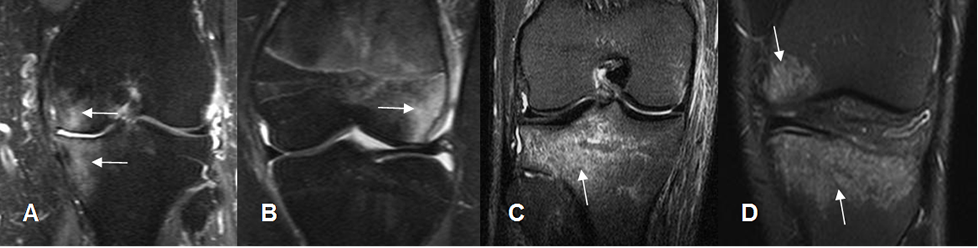

Fig 39. Mecanismo del trauma directo.

A: RM coronal en STIR. Contusión osea en el compartimiento medial, que puede lesionar las estructuras de la esquina posterolateral y el LCL.

B: RM coronal en STIR. Contusión del cóndilo femoral lateral, debiendo descartar lesión del LCM.

C: RM coronal en STIR. Contusión en la parte posterior de la tibia, por lo que se debe buscar lesión del LCA

D: Contusión en la parte anterior de la tibia y cóndilo femoral medial, a descartar lesión del LCP y esquina posterolateral.